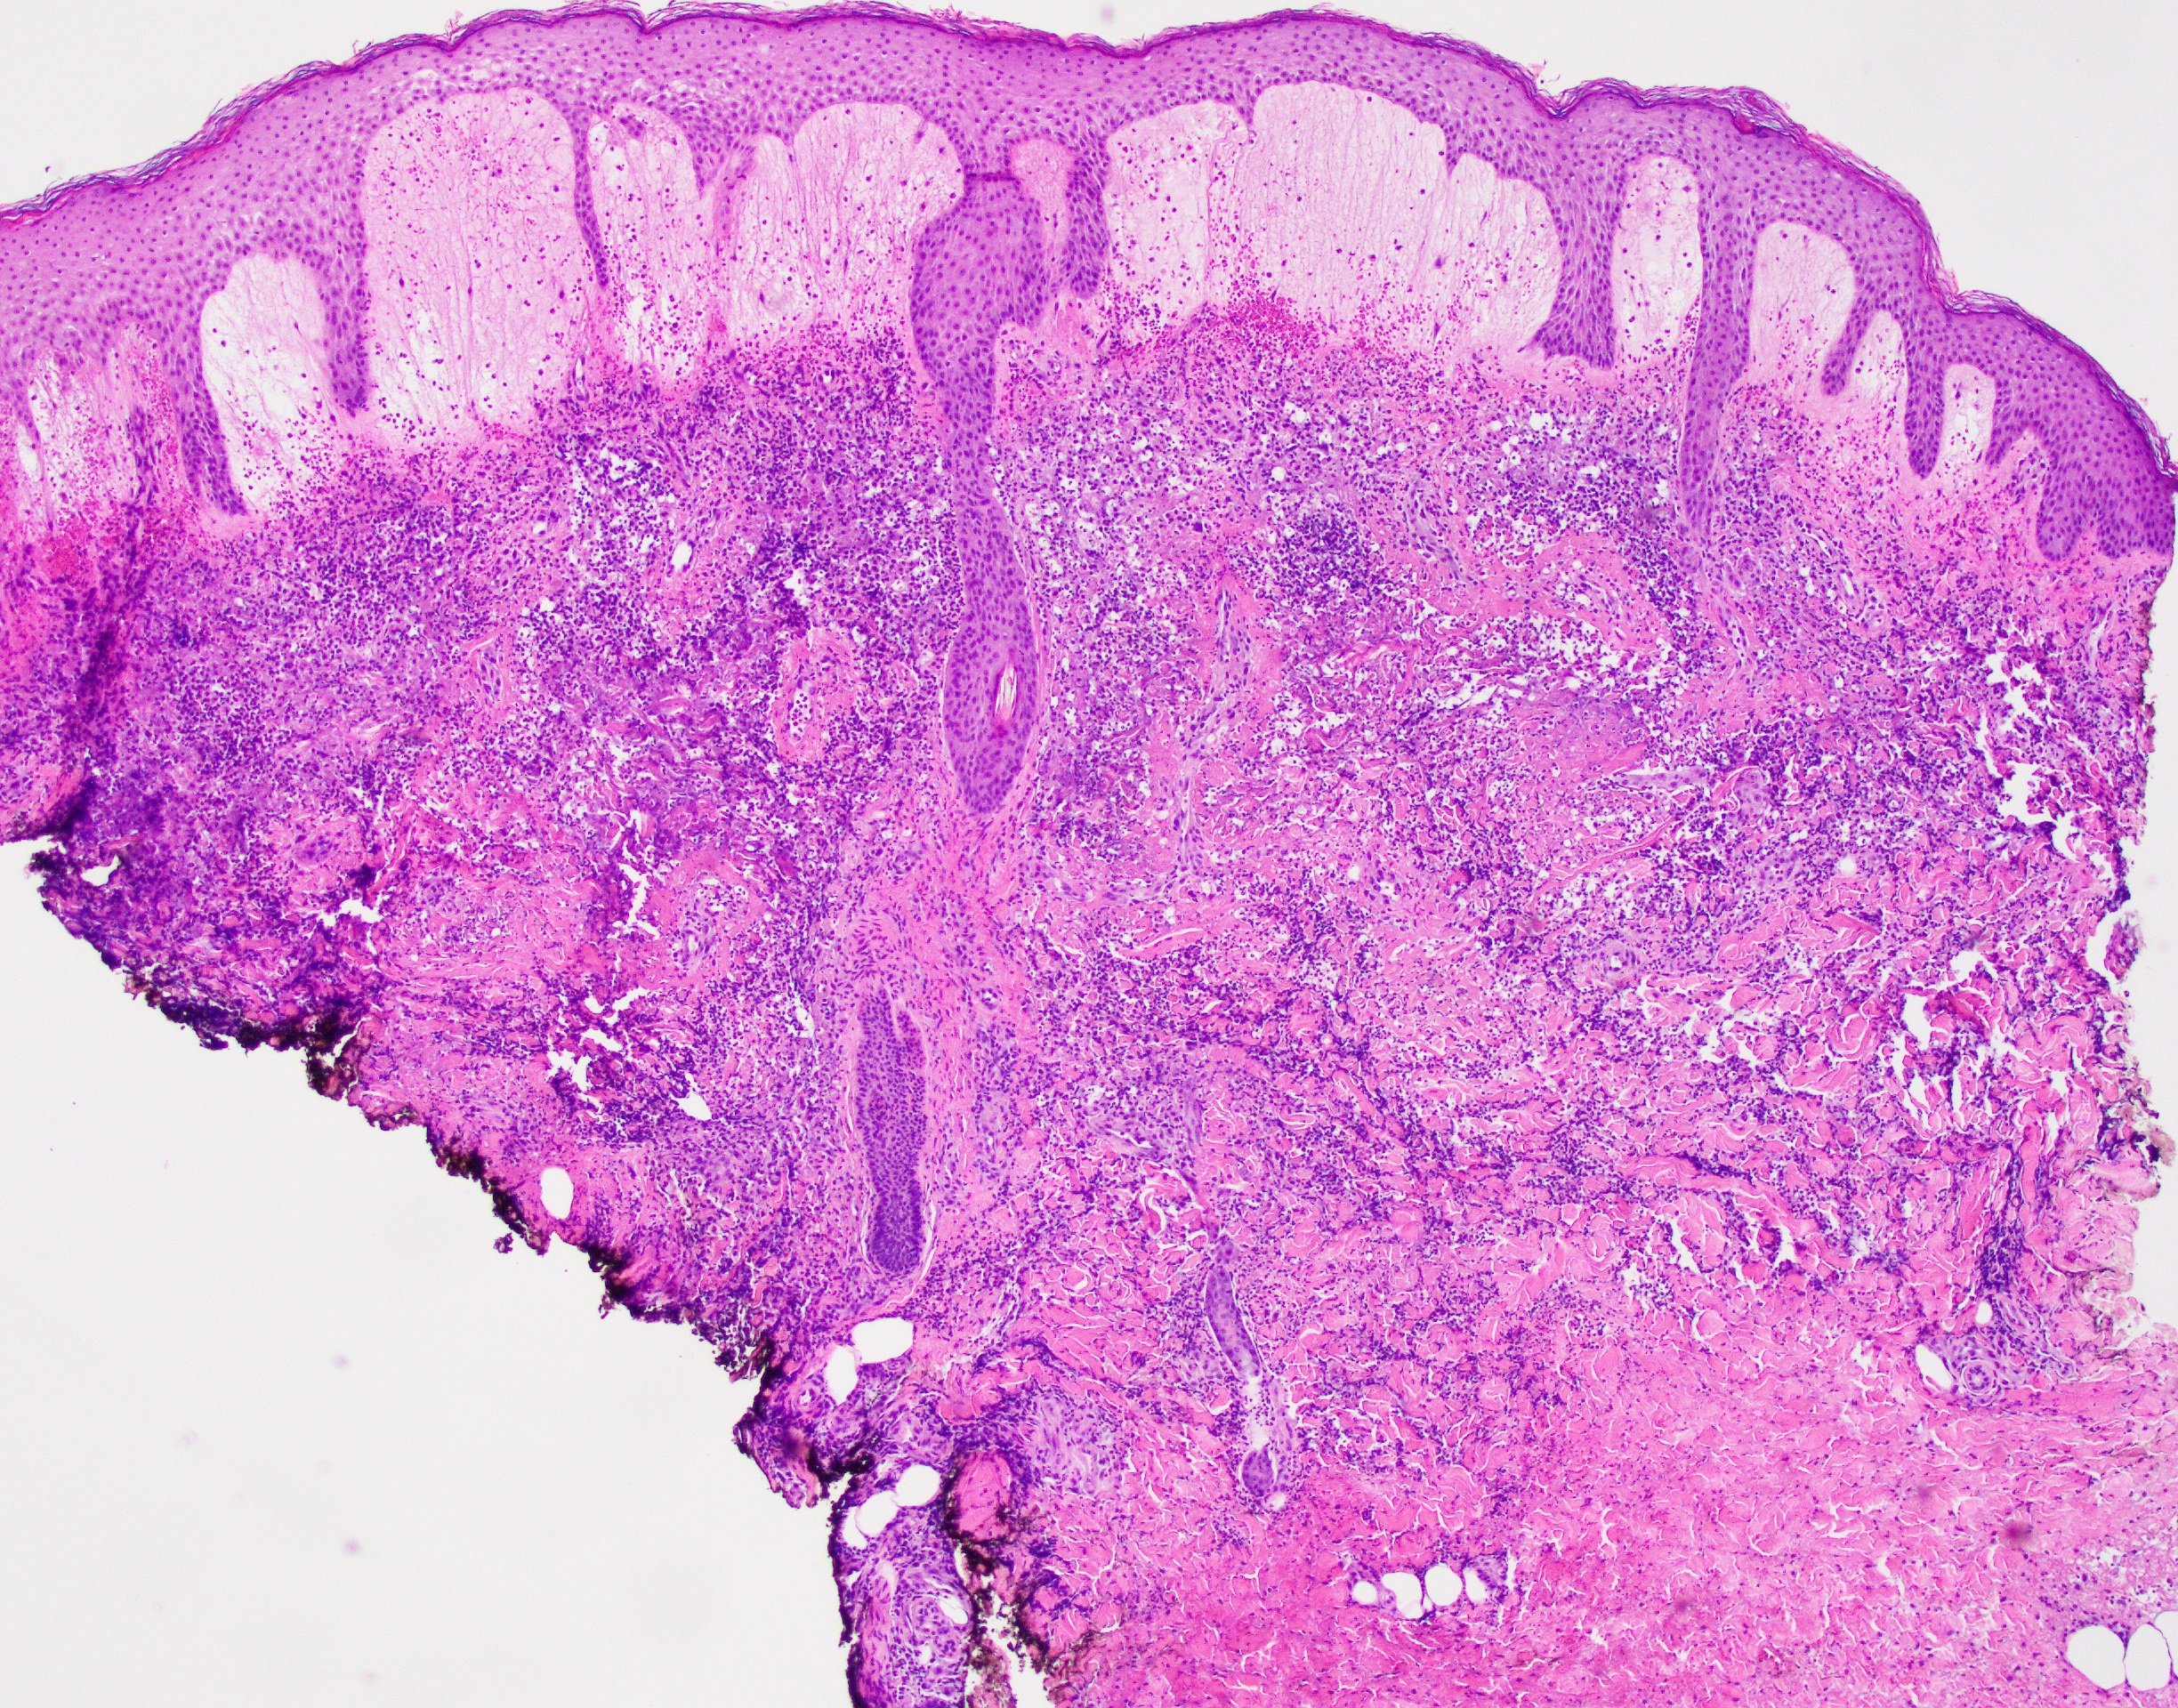

Picture144 year old female with 2.8 cm midline tongue mass

What's the underlying condition?